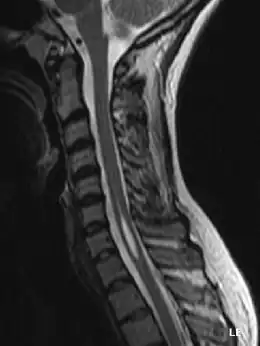

Description de l'image syringomyelia.jpg.

L'imagerie par résonance magnétique est l'examen clef[7]. Il permet de mettre en évidence une cavité oblongue à l’intérieur de la moelle, remplie de liquide cérébrospinal en regard de plusieurs vertèbres. Toutefois son interprétation doit être discutée car la présence de cette cavité pourrait aussi être le vestige d'un canal central non collabé issu de l’embryogenèse. Ainsi il est important de confronter ce résultat à la présence éventuelle d'autres causes pathogéniques : malformation de Chiari, scoliose, distension de moelle spinale, traumatisme de voisinage…